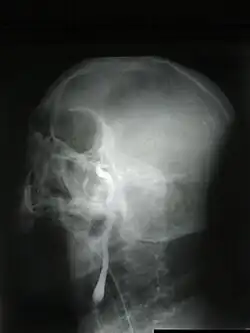

- Do wykazania zmian w mózgowiu świadczących o jego ciężkim uszkodzeniu, które może być przyczyną śpiączki i śmierci mózgu, wykorzystywane są najczęściej badania tomografii komputerowej (TK) i rzadziej, rezonansu magnetycznego (MR), a u noworodków i niemowląt także badania przezciemiączkowe usg.

- Najczęstszymi zmianami stwierdzanymi w pierwotnym uszkodzeniu mózgu są masywne krwawienie (samoistne albo pourazowe) lub niedokrwienie. Ponadto w badaniach neuroobrazowych typowo obserwuje się cechy uogólnionego obrzęku mózgu. Mogą one występować pod postacią spłaszczenia zakrętów i zaciśnięcia przymózgowych przestrzeni płynowych – bruzd i zbiorników podstawy, zmniejszenia zróżnicowania między istotą szarą a istotą białą lub wgłobienia: migdałków móżdżku w otwór wielki, zakrętu obręczy pod sierp mózgu, pnia mózgu w otwór wielki, zakrętu przyhipokampowego we wcięcie namiotu móżdżku. W obrazach T2-zależnych MR widoczne jest zwiększenie sygnału obejmujące przede wszystkim istotę szarą. W obrazowaniu dyfuzji wody metodą MR (DWI) w fazie obrzęku cytotoksycznego obserwuje się uogólnioną restrykcję dyfuzji.

- Kolejnym objawem widocznym w obrazach T2-zależnych jest brak fizjologicznie występującego zjawiska zaniku sygnału w naczyniach mózgowych. Świadczy to o skrajnym upośledzeniu albo zatrzymaniu krążenia mózgowego. W uszkodzeniach wtórnych w mechanizmie niedotlenieniowo-niedokrwiennym spowodowanym zatrzymaniem krążenia, albo zapalnym, zmiany są zazwyczaj słabiej wyrażone i pojawiają się później niż w uszkodzeniach pierwotnych.

- W wątpliwych przypadkach badanie obrazowe należy powtórzyć po pewnym czasie lub w dalszym postępowaniu diagnostycznym zastosować badanie instrumentalne.